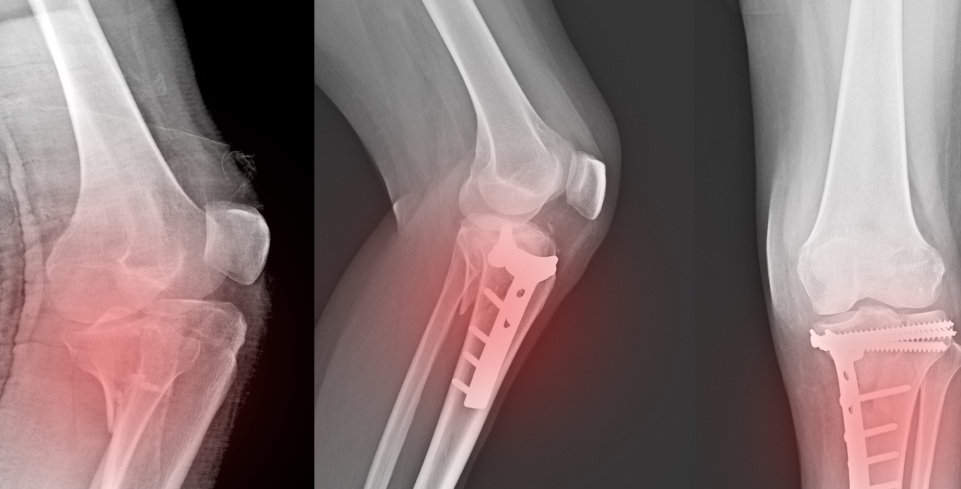

No joelho, as fraturas de estresse acometem principalmente a tíbia proximal, o fêmur distal e, em alguns casos, a patela. Esse tipo de lesão é comum em atletas, corredores, militares e pessoas que aumentam repentinamente a intensidade ou o volume de atividades físicas, mas também pode afetar indivíduos sedentários que iniciam exercícios sem orientação adequada.

A radiografia simples pode não identificar a fratura de estresse nas fases iniciais. Por isso, a ressonância magnética é o exame de escolha, pois permite detectar precocemente alterações ósseas e inflamatórias. Em alguns casos, a cintilografia óssea também pode ser utilizada.

A cirurgia é rara, mas pode ser necessária em fraturas de estresse de alto risco, quando não há consolidação óssea ou quando ocorre progressão da lesão apesar do tratamento conservador.